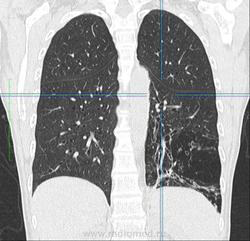

Женщина 50 лет, поступила в стационар с жалобами на субфебрилитет, постоянно рецидивирующие бронхит и пневмонию на протяжении 2 лет. Выполнена ФЛГ - подозрение на сегментарную инфильтрацию в верхней доле правого легкого, повышена воздушность нижней доли левого легкого.Выполнена КТ - с чем бы Вы дифференцировали процесс, коллеги?

Выложил ключевые изображения, толщиной 5 мм, легочное окно, Kernel 90. Если требуется DICOM - выложу позже

вообще то это зона фиброателектаза с тракционными бронхоэктазами(слева ),справа в верхней доле многогоузловое с утолщенным интерлобулярным интерстицием переходящим на междолевую плевру (локальное утолщение ее ),признаков тракции ее не обнаружено,на фронталах по периферии крупного узла утолщенный интралобулярный интерстиций(локального лимфостаза не обнаружено )-вообщем все старое .хотелось бы на все в медиастинальном окне посмотреть ,а так специфику с неспицификой

Да ладно Вам,какой же это фиброателектаз?Я бы скорее подумала о секвестрации.В артериальную фазу при контрастировании можно увидеть аберрантный сосуд,связанный с аортой .Заодно решите проблему справа.Для более точной диагностики посмотрела бы все исследование,т.к.представленных сканов недостаточно.Какая-то кистозная дисплазия в S10слева имеется,похоже и на бронхоэктазы.Вот основные направления,над которыми надо работать.

при всем уважении к вам коллега не соглашусь с вами т.к.объем то нижней доли слева уменьшен(первый скан это 100% показывает ) -четкие вогнутые контуры на фоне сближенного легочного рисунка ,говоря даже ренгенологическим ,а не радиологическим языком +тракция бронхов неменуемо подталкивают на использованный мною термин (пусть будет фиброгиповентиляция -словами можно играть сколь угодно)-но механизм я объяснил.возрастные нормативы всегда беру при постановке диагноза +анамнез не противоречит синдрому.при секвестрациях объем не уменьшен ,да и всегда есть четкая солидная часть.мальформация у нас 3 типов и все не подходят ,да и где гипоплазия левого легкого,с уважением федя.

У больной бисегментарная инфильтрация в верхней доле правого легкого. Какой этиологии пока неизвестно, возможно и TB (клиника очень стертая, сдали мокроту на КУМ).

Насчет изменений в нижних отделах - то описал их как диффузные структурные изменения прам-пам-пам с развитием центрилобулярной эмфиземы.

Там и циллиндрические бронхоэктазы, и центрилобулярная эмфизема. В обоих легких, больше в левом. Бронхиолы сильно расширены, практически до субплевральных отделов, причем бронхоэктазы есть не только в нижних отделах, но и в верхних. На последней 3Д реконструкции неплохо отображено бронхиальное дерево. оно патологическое.